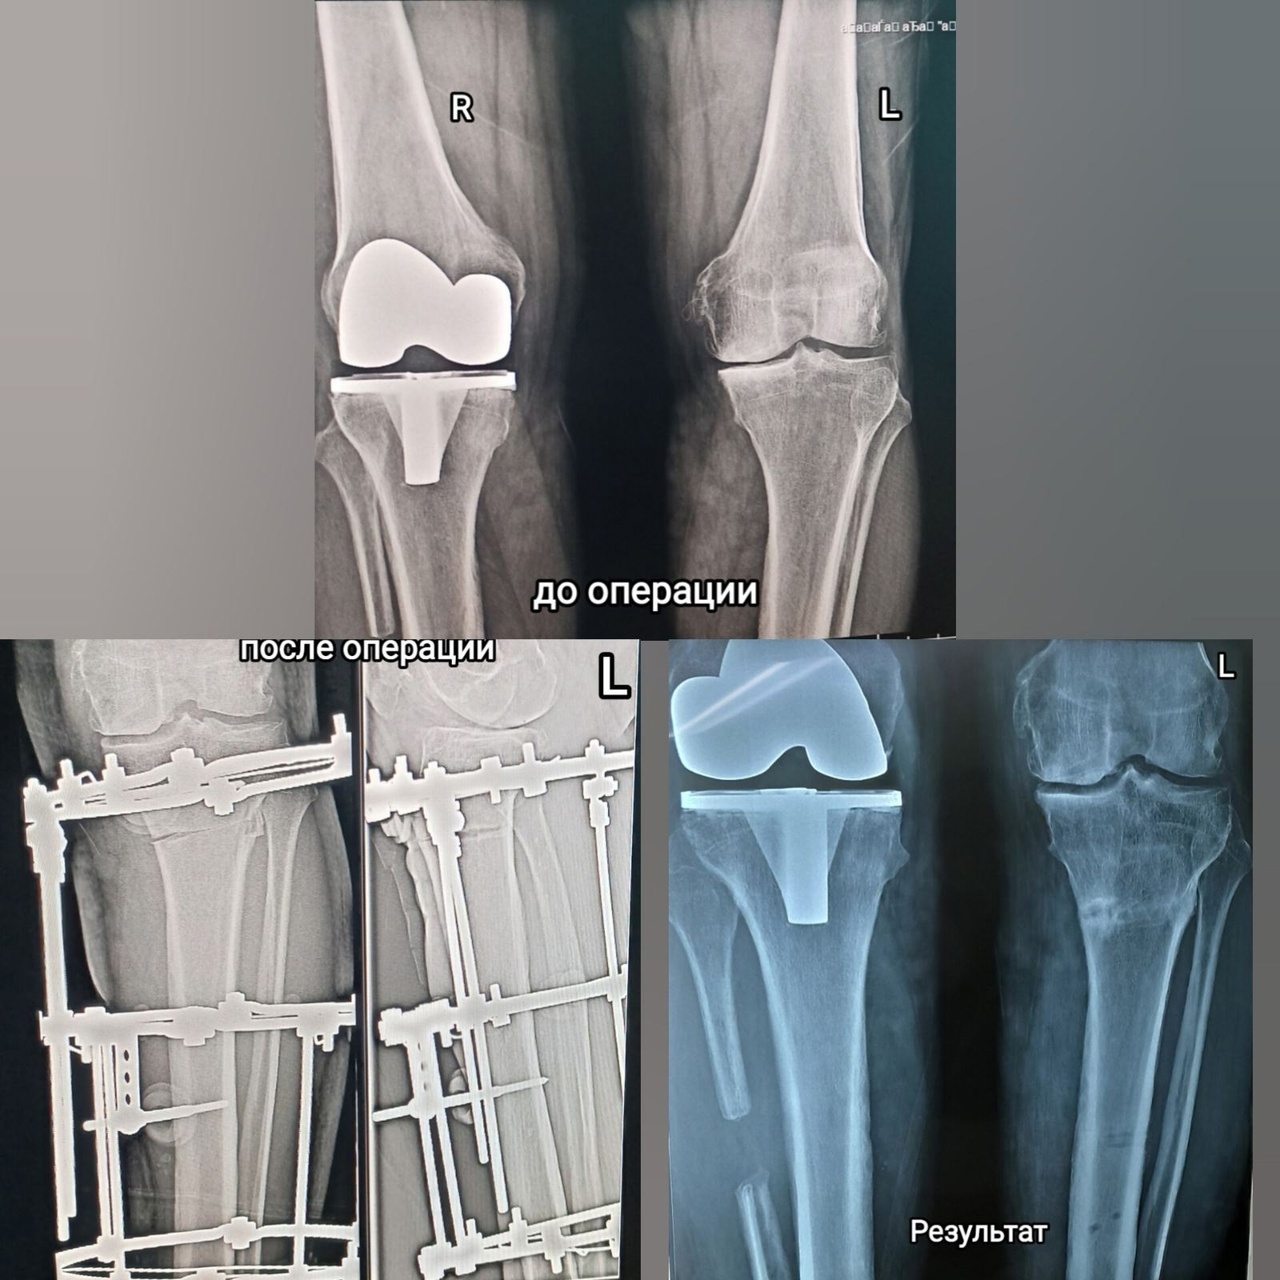

Николай Галушко страдал от проблем с правым коленом. Он мог вставать только с четверенек, ощущая режущую боль до слез. При этом на работе ему приходилось подниматься и спускаться ежедневно с 4 этажа. После двух операций в 2022 году в Тюмени и Ишиме у него возникли новые проблемы с ногами и позвоночником из-за разной длины конечностей.

Врачи ОБ №4 предложили Николаю органосберегающую операцию на левой голени, и он согласился. Процедура прошла под спинальной анестезией. В течение пяти месяцев его ногу вытягивали и выпрямляли с помощью аппарата Илизарова.

После всех процедур мужчина доволен результатом и советует доверять врачам. Он благодарен доктору Парвинжону Азимову за помощь в возвращении к полноценной жизни.

Фото: Здравоохранение Тюменской области